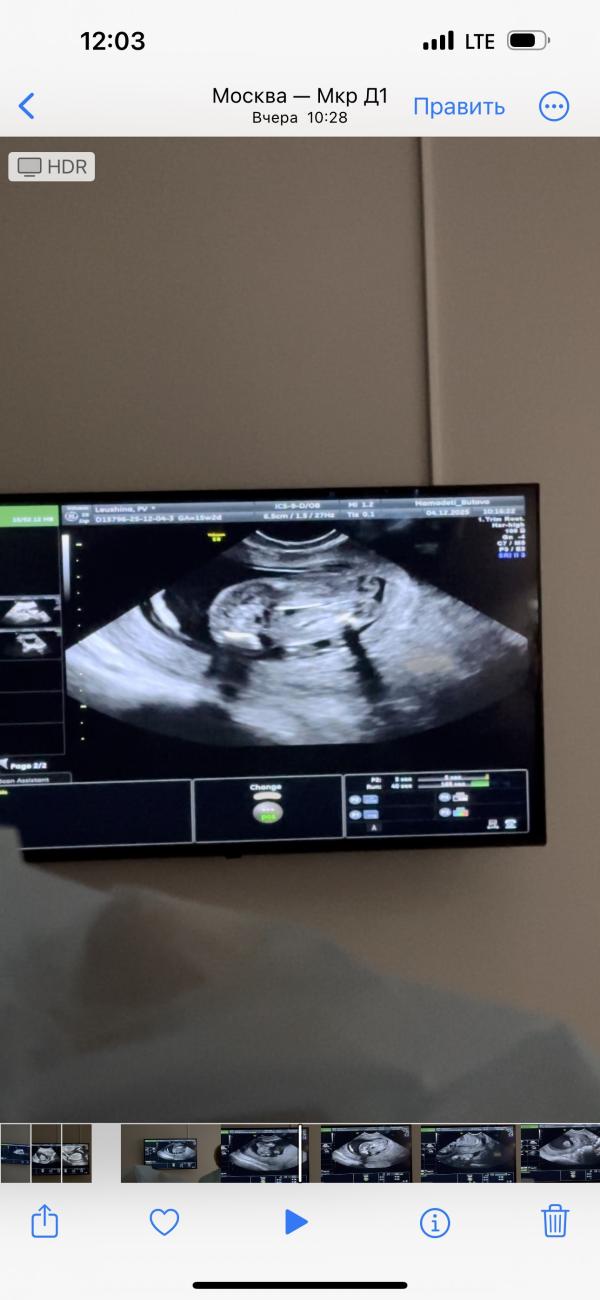

Девочки, делала узи вчера, 15 неделя, сказали что девочка.

Но меня смущает, что как-то быстро определили по первым двум снимкам (вид снизу).

И + смущает вид сзади (следующие три фото), как будто что-то торчит.

Ножки были сильно сомкнуты у малыша.

Торчит это скорее всего половой бугорок, у девочек он вниз смотрит, а у мальчиков кверху.